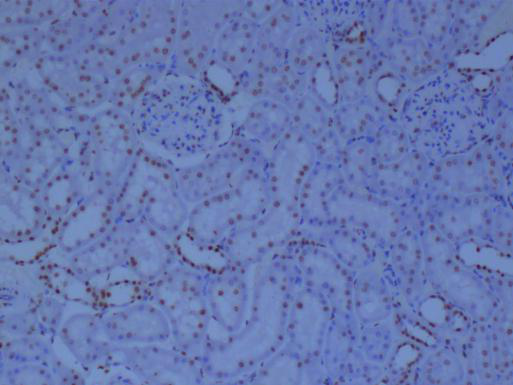

二、免疫組化:細(xì)胞與組織中的分子指紋

免疫組化技術(shù),則更多地被用于組織和切片水平的分析。通過特異性抗體與抗原的結(jié)合,結(jié)合顯色系統(tǒng),可以在組織切片上呈現(xiàn)出目標(biāo)蛋白質(zhì)的表達(dá)情況,為疾病的診斷和病理學(xué)研究提供重要依據(jù)。

①高特異性:特異性抗體能夠精確識別目標(biāo)蛋白質(zhì)。

②組織定位:能夠在組織切片上呈現(xiàn)目標(biāo)蛋白質(zhì)的分布和表達(dá)情況,對于疾病的定位診斷具有重要意義。